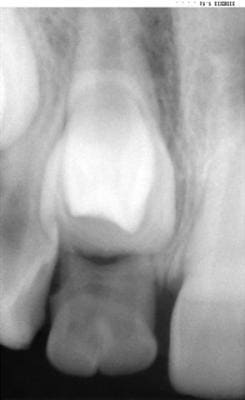

Patiente 9ans, retard de l'évolution de la 11 par chute prématurée de la 51. Aquoi correspond cette image radio? J'ai prévu de mettre un sectionnel 21-12-22 et un UA afin de garder la position de mes incisives dans le sens antéro- postérieur. Que feriez- vous dans ce cas.

peut être une "dens in dente"?

Moi aussi, j'aurais pensé à une dens in dente.

dens in dente d'apres moi aussi

retard d'eruption du a la forme elargie de la 11

je ferais extraction de la 51(geminee) et surveillance particuliere de la 11

ces dents sont plus sujettes aux caries de par leur forme et les traitements canalaires compliques (communication des pulpes au niveau du cingulum)

Il y a de grandes chances qu'il ne s'agisse pas pas d'une dens in dente mais d'un élement surnuméraire (odontoîde)qui bloque la rhyzalyse de 51 et l'éruption de la 11 .Vu l'age de l'enfant et le développement radiculaire de la 11 il y a urgence à agir: extraction de la 51 géminée et de l'odontoîde.Puis srveillance pendant 6 à 9 mois .Si la dent n'évolue pas de façon naturelle il faudra la tracter orthodontiquement.